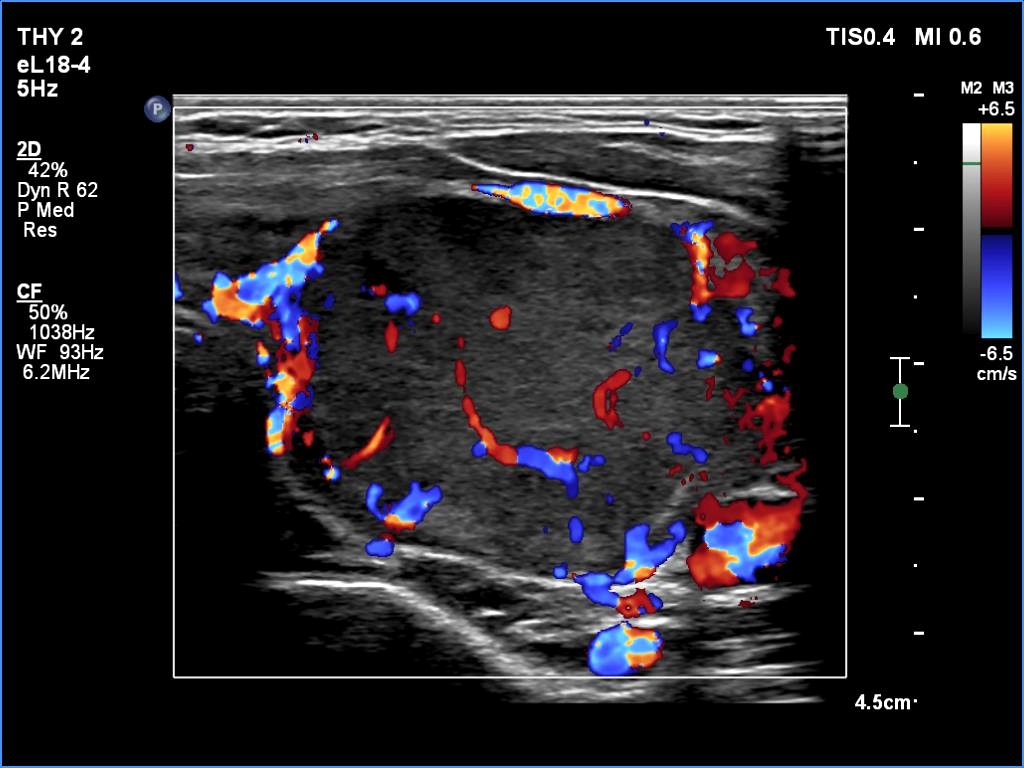

The echogenicity of the nodule - case 365 (ultrasonographic picture 8)

Five years after the first examination

Left lobe, transverse scan, color Doppler mode. Compared with the previous examination, intranodular blood flow has appeared.